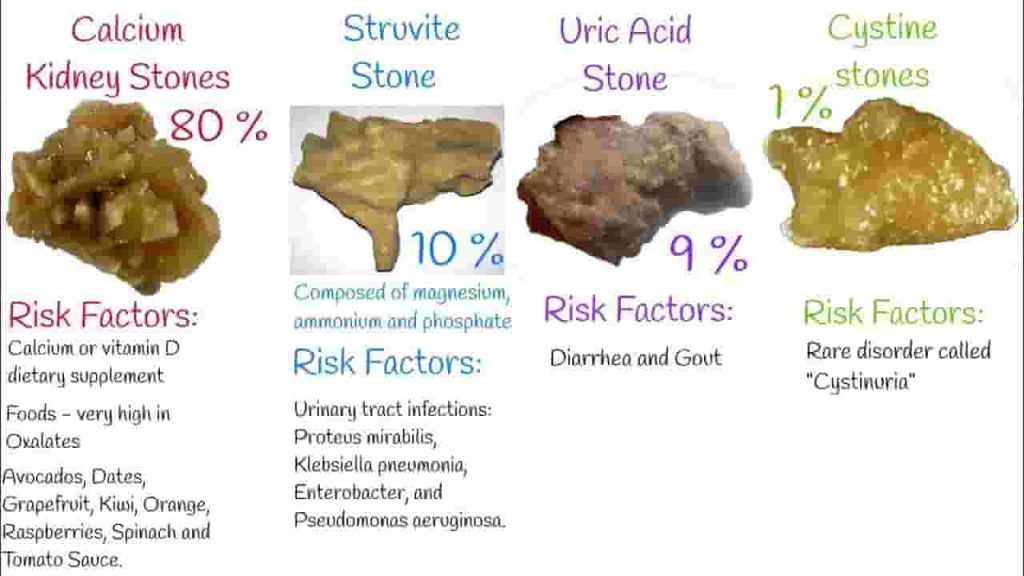

شناخت انواع سنگ ھای کلیه

سنگ کلیه کلسیمی

سنگ کلیه اسید اوریکی

سنگ کلیه سیستینی

سنگ کلیه استروایتی

عوامل خطر سنگ کلیه: چه کسانی بیشتر در معرض خطر سنگ کلیه هستند؟